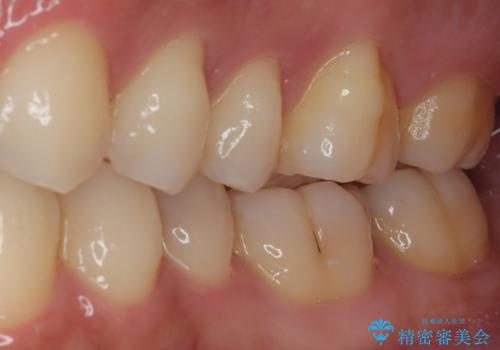

フロスがちぎれることもなくなり、被せものが入っていることを忘れていたと大変喜んでいただきました。適合の良い被せものは二次的な虫歯の再発リスクを低減してくれます。

今後の予定は患者様のタイミングで歯茎から少し見えている親知らず抜歯を行っていく予定です。